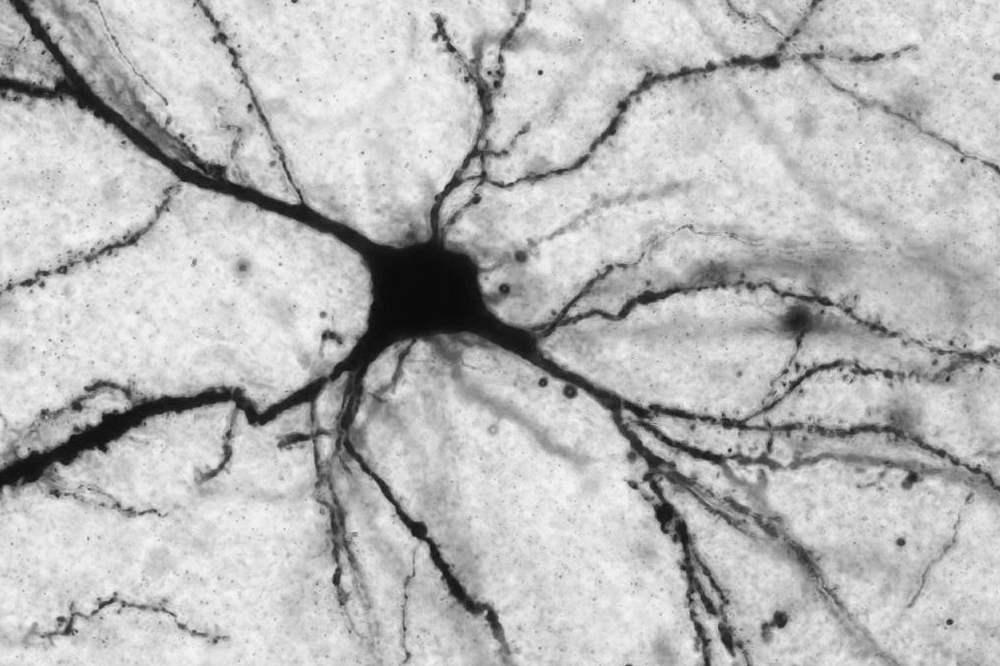

Naturally produced by the body, LAC performs a number of crucial tasks in the brain. For example, the molecule regulates energy metabolism and interacts with DNA to promote the expression of important genes. Specifically, it acts on a gene that controls levels of the neurotransmitter glutamate—a chemical implicated in almost everything that the brain does.

McEwen, the Alfred E. Mirsky Professor, and Nasca, a postdoctoral fellow of the American Foundation for Suicide Prevention, have studied the link between LAC and mood disorders using animal models. In one study, they showed that LAC supplements ameliorate depressive symptoms in mice by reversing brain-cell impairment caused by an excess of glutamate. In a separate rodent study, they observed that LAC treatment reduces depressive behavior and stress-associated neural dysfunction in the medial amygdala, a brain region involved in social interactions. These findings strongly suggest that LAC deficits contribute to a depression-like state in mice, leading the scientists to wonder whether the molecule plays a similar role in humans.